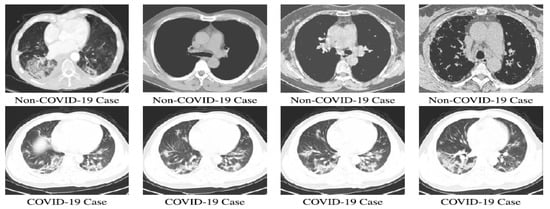

4.1. Experimental Results on CT Images

| Proposed System | Major voting classifier is used for reducing the classifier bias. Outcomes of ResNet 50, ResNet100, ResNet101, VGG 16, and VGG 19 are given as input to the major voting classifier. It selects the majority voted one. Image data generator used for synthetic data generation. | Data analysis is one of the modules used in making the system automated. Pre-trained models are used for image analyses. Totally, 7455 CT images and 8900 X-ray images are considered for experimentation. |

| 1700 (images collected from public resource) + 7455 (synthetic data) | CT | ResNet 50 | Precision | 78% |

| 1700 (images collected from public resource) + 7455 (synthetic data) | CT | ResNet 100 | Precision | 92% |

| 1700 (images collected from public resource) + 7455 (synthetic data) | CT | ResNet 101 | Precision | 97% |

| 1700 (images collected from public resource) + 7455 (synthetic data) | CT | VGG 16 | Precision | 89% |

| 1700 (images collected from public resource) + 7455 (synthetic data) public resource) + 7455 (synthetic data) | CT | VGG 19 | Precision | 97% |